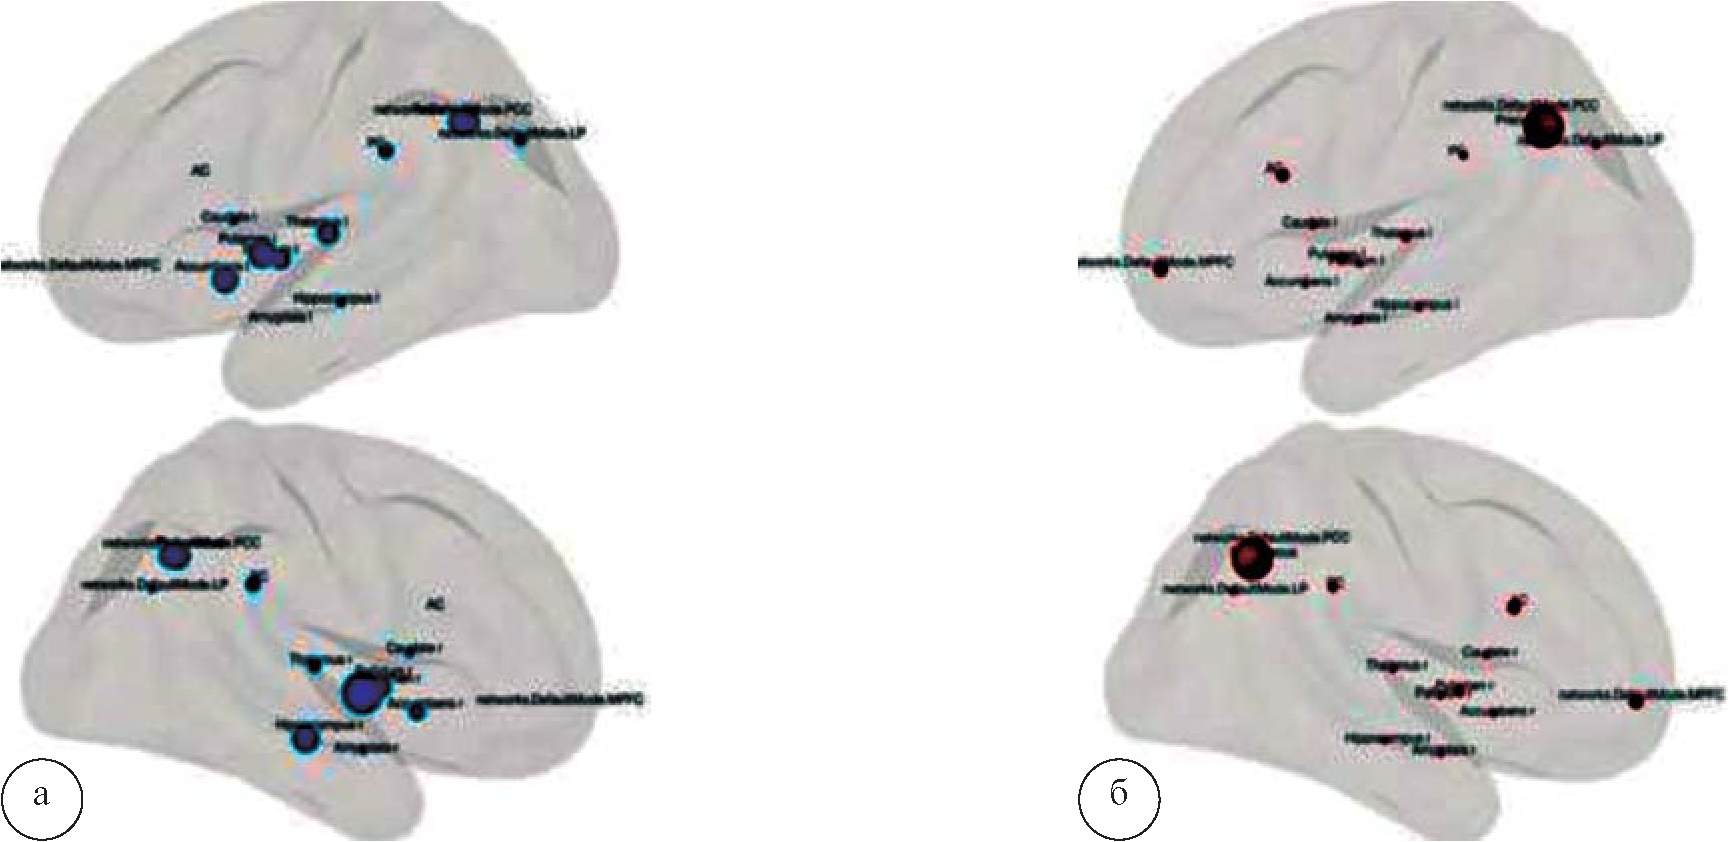

На рисунке 6 продемонстрированы объемные модели коннективности структур головного мозга при групповом анализе при синдроме зависимости от опиоидов и в норме. Отмечается разобщение нижних и средних отделов орбитофронтальной коры. Единственным участком орбитофронтальной коры, непосредственно связанным с субкортикальными структурами, остается верхний ее отдел. Отсутствуют взаимосвязи между различными отделами МЛО.

Рис. 6. Коннективность головного мозга на основе анализа графов: а – при опиоидной наркомании; б – в норме, p<0,05. Сферы символизируют корковые и подкорковые структуры, связи помечены линиями. Отмечается значительное обеднение набора связей при наркозависимости